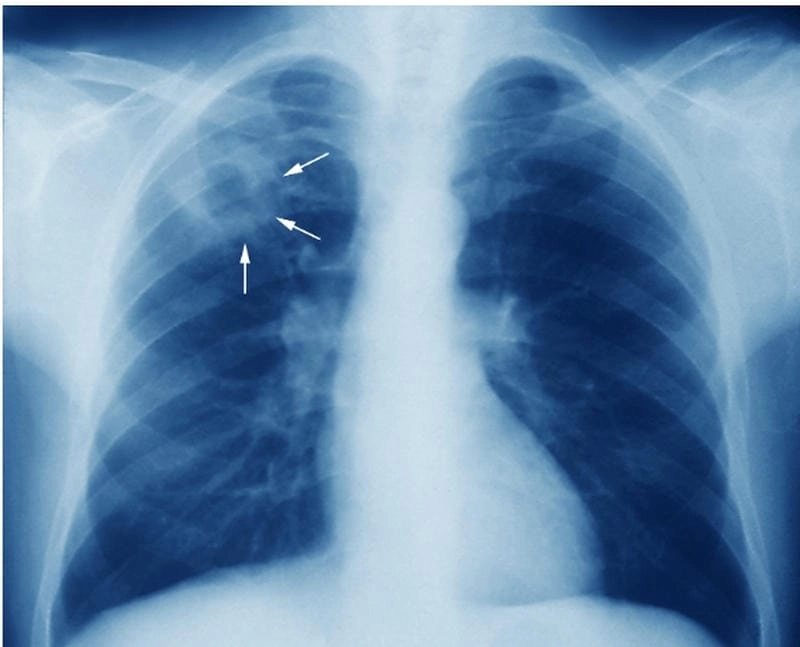

Hình ảnh bệnh lao phổi là tài liệu tham khảo quan trọng giúp người bệnh và bác sĩ dễ dàng nhận biết dấu hiệu bất thường. Việc quan sát hình ảnh X-quang, CT phổi giúp chẩn đoán chính xác mức độ tổn thương và đưa ra phương án điều trị kịp thời.

Bạn sẽ phải rùng mình khi chiêm ngưỡng hình ảnh bệnh lao phổi là như thế nào dưới ống kính y học thực tế. Những bức ảnh chụp X-quang cho thấy phổi bị tổn thương nặng, xuất hiện những đốm trắng mờ như bóng ma ám ảnh. Không chỉ là các tổn thương vật lý, đây còn là những “chứng tích sống” của căn bệnh âm thầm hủy hoại cơ thể qua từng hơi thở. Từ viêm nhẹ đến tổn thương lan rộng, hình ảnh bệnh lao phổi khiến người xem không thể rời mắt vì mức độ nghiêm trọng mà nó thể hiện rõ ràng qua từng chi tiết.

Cảnh báo: tổng hợp ảnh bệnh lao phổi chân thực này không dành cho người yếu tim. Đây là loạt hình ảnh y khoa được các chuyên gia sưu tầm và xác thực, ghi lại quá trình tiến triển của bệnh từ giai đoạn đầu đến giai đoạn nguy kịch. Từng mảng mô phổi bị ăn mòn, xơ hóa, hoại tử được phơi bày rõ nét dưới ánh sáng X-quang lạnh lùng. Những hình ảnh này không chỉ mang tính chất minh họa y học, mà còn là hồi chuông cảnh tỉnh cho bất kỳ ai còn lơ là với căn bệnh nguy hiểm này.